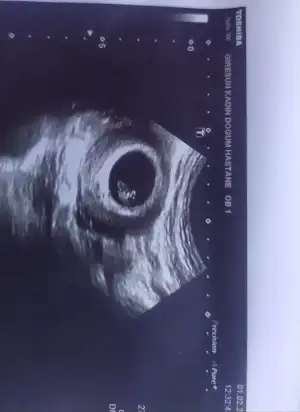

Bence bekleyin. Kendi doktorunuzu dinleyin henüz çok küçük . İnşallah o doktor yanılıyordur. Benim inancım o yönde. Dualarım sizinle1hafta önce kendi doktoruma gitmiştim o kese yeni oluşmuş 4 haftalık dedi hic takilmamisti güne 3 hafta sonra kalp atışına çağırmıştı

Bence de bebek görünüyor ama bilemedim canımBen erken gittim canım düşük iğnesi kullaniyorum aslında onu danışmak icin gitmistim. 1 hafta gecti sadece.bebek var mı diyosunuz doktor bana hic hareket yok dedi kalp atışı için bebek hakkında bişey demedi

Bnim kesem bile 6+7 Ken böyleydi inşallah Allah'ın izniyle bebeğini sağ sağlım kucağına alıcaksınCok tesekkur ederim inşallah.haber veririm mutlaka

Sağ alttaki crl değeriniz ne yazıyor acBaBanada bakarmısınız o zaman canımkarından ultrason 6+3

Canım 6+4 te 6 mm idiKızlar selamlar

Burda gözüküyorSağ alttaki crl değeriniz ne yazıyor acBa